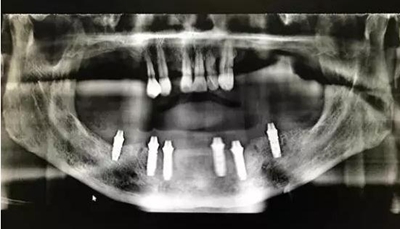

全程手術(shù)采用小翻瓣微創(chuàng)種植,選擇初期穩(wěn)定性較好的植體進(jìn)行即刻負(fù)重。整個手術(shù)從開始到最終戴上臨時牙,只花費2個小時的時間,就讓患者恢復(fù)了完美笑容。數(shù)字化種植為醫(yī)生和患者帶來不一樣的感受!